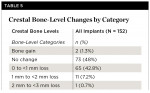

Radiographs were available for 152 implants. The average change from implant surgery to 1-year follow-up was -0.3 mm ± 0.46 mm. No significant differences were seen between the mesial and distal aspects, so they were combined in Table 4, which provides a summary of crestal bone-level values and changes.

Subjects were categorized into groups based on the change in bone level from implant surgery to 1-year follow-up. Most of the subjects (>90%) showed either no bone remodeling or less than 1 mm bone loss. Two subjects (1.3%) had bone gain.Crestal bone-level changes by category are presented in Table 5.